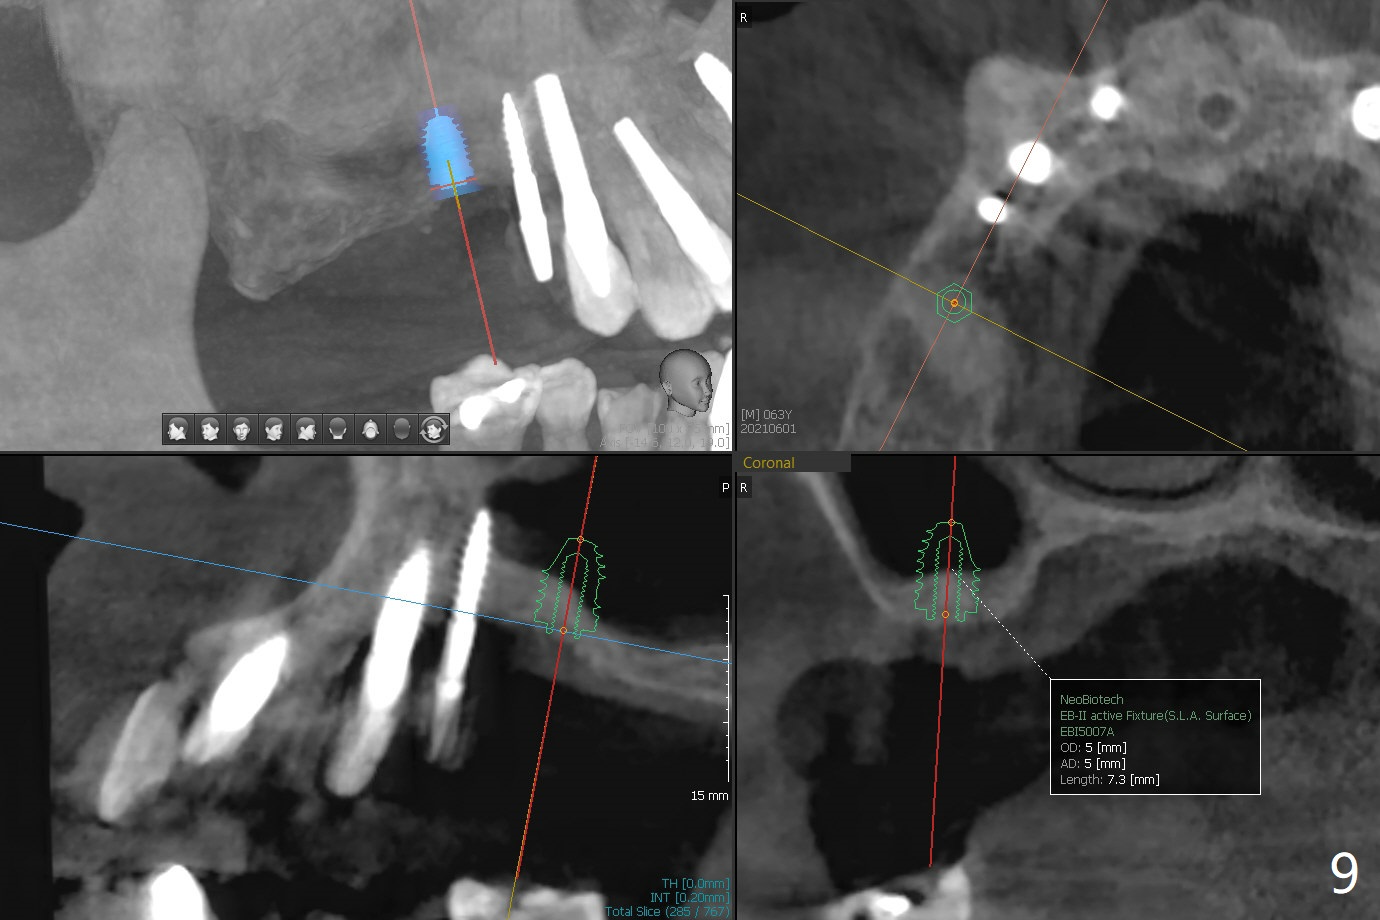

术前检查发现右上6颊侧牙龈沟有脓性分泌物(图一),翻瓣显示骨质吸收(图二),曾经植骨三次,只好去骨,取出植体,远中颊侧轻度上颌窦穿孔(图三:>),塞入小块PRF膜后,患处放置粘性骨粉,覆盖两块PRF膜和一片GEM Cap(9-12月吸收膜),三者近中一端有一个洞,挂在5基台上固定。术后即刻根尖片显示骨粉充填穿孔(图四:>),6缺失区以及5远中(*)。术后第二天牙周敷料脱落,术后16天病人回来,要求剪除缝线,伤口尚未关闭,下面黄色骨粉好像挺牢靠;为了减少继续骨粉丧失,使用树脂敷料(图五)。术后四周敷料稳定,牙龈健康,但是不放心下面伤口愈合,暂时没有撤去敷料。术后四个月骨质高度不足(图六至八),上颌窦膜薄,提升不容易,可放置5x7.3毫米植体(IBS),PRF。Return to No Caries 4 Placement 种植杂谈 Xin Wei, DDS, PhD, MS 1st edition 01/26/2021, last revision 07/30/2021